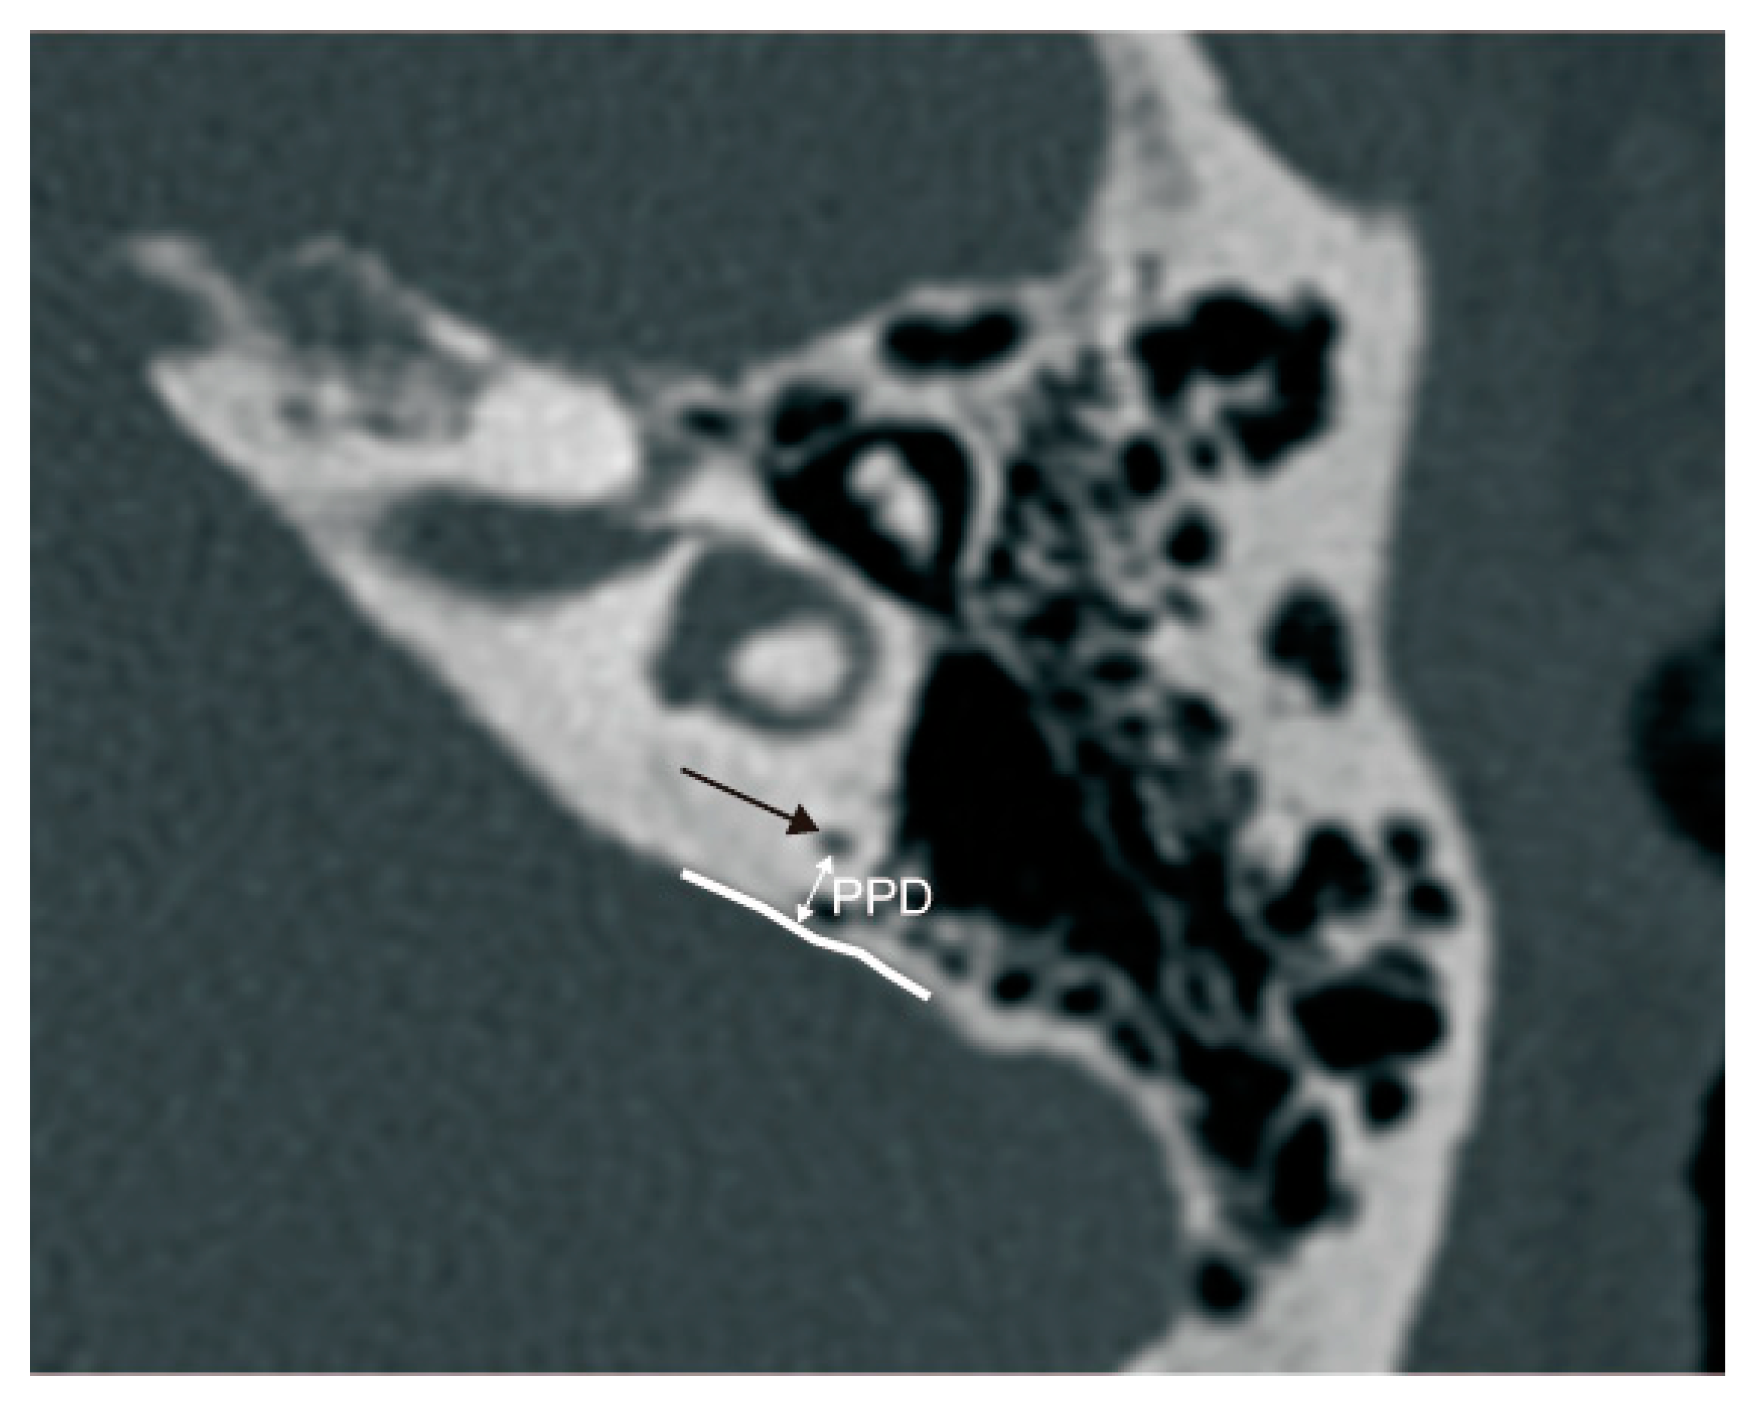

The PPD was measured between the vertical part of the posterior semicircular canal and the posterior fossa on axial panel [11] (Figure 4).

Figure 4.

The measurement of the vertical part of the posterior semicircular canal—the posterior fossa distance (PPD). Black arrow: the vertical part of the posterior semicircular canal; white curve: the anterior boundary of the posterior fossa.